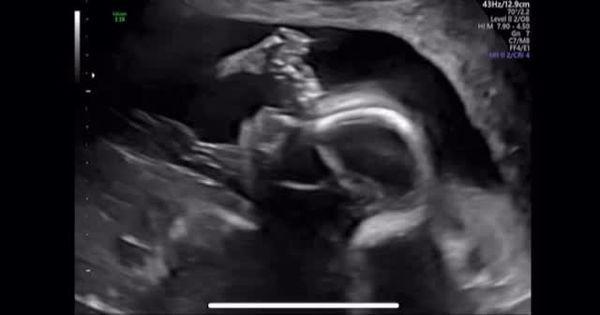

另外,林正姬也提到宝宝的胎名叫「BongBong」,并分享一段超音波的影片,可见宝宝在妈妈肚子里十分活泼。事实上,林正姬与小6岁的芭蕾舞者金熙然(音译)交往一年后,于2023年10月步入婚姻。金熙然曾是韩国国立芭蕾舞团的独舞者,并曾在芭蕾经典《吉赛尔》中担任主角,是一位备受肯定的专业舞者。

宝宝的胎名是BongBong我会稍微让大家看看他在妈妈肚子里动着嘴巴的可爱模样。金年会